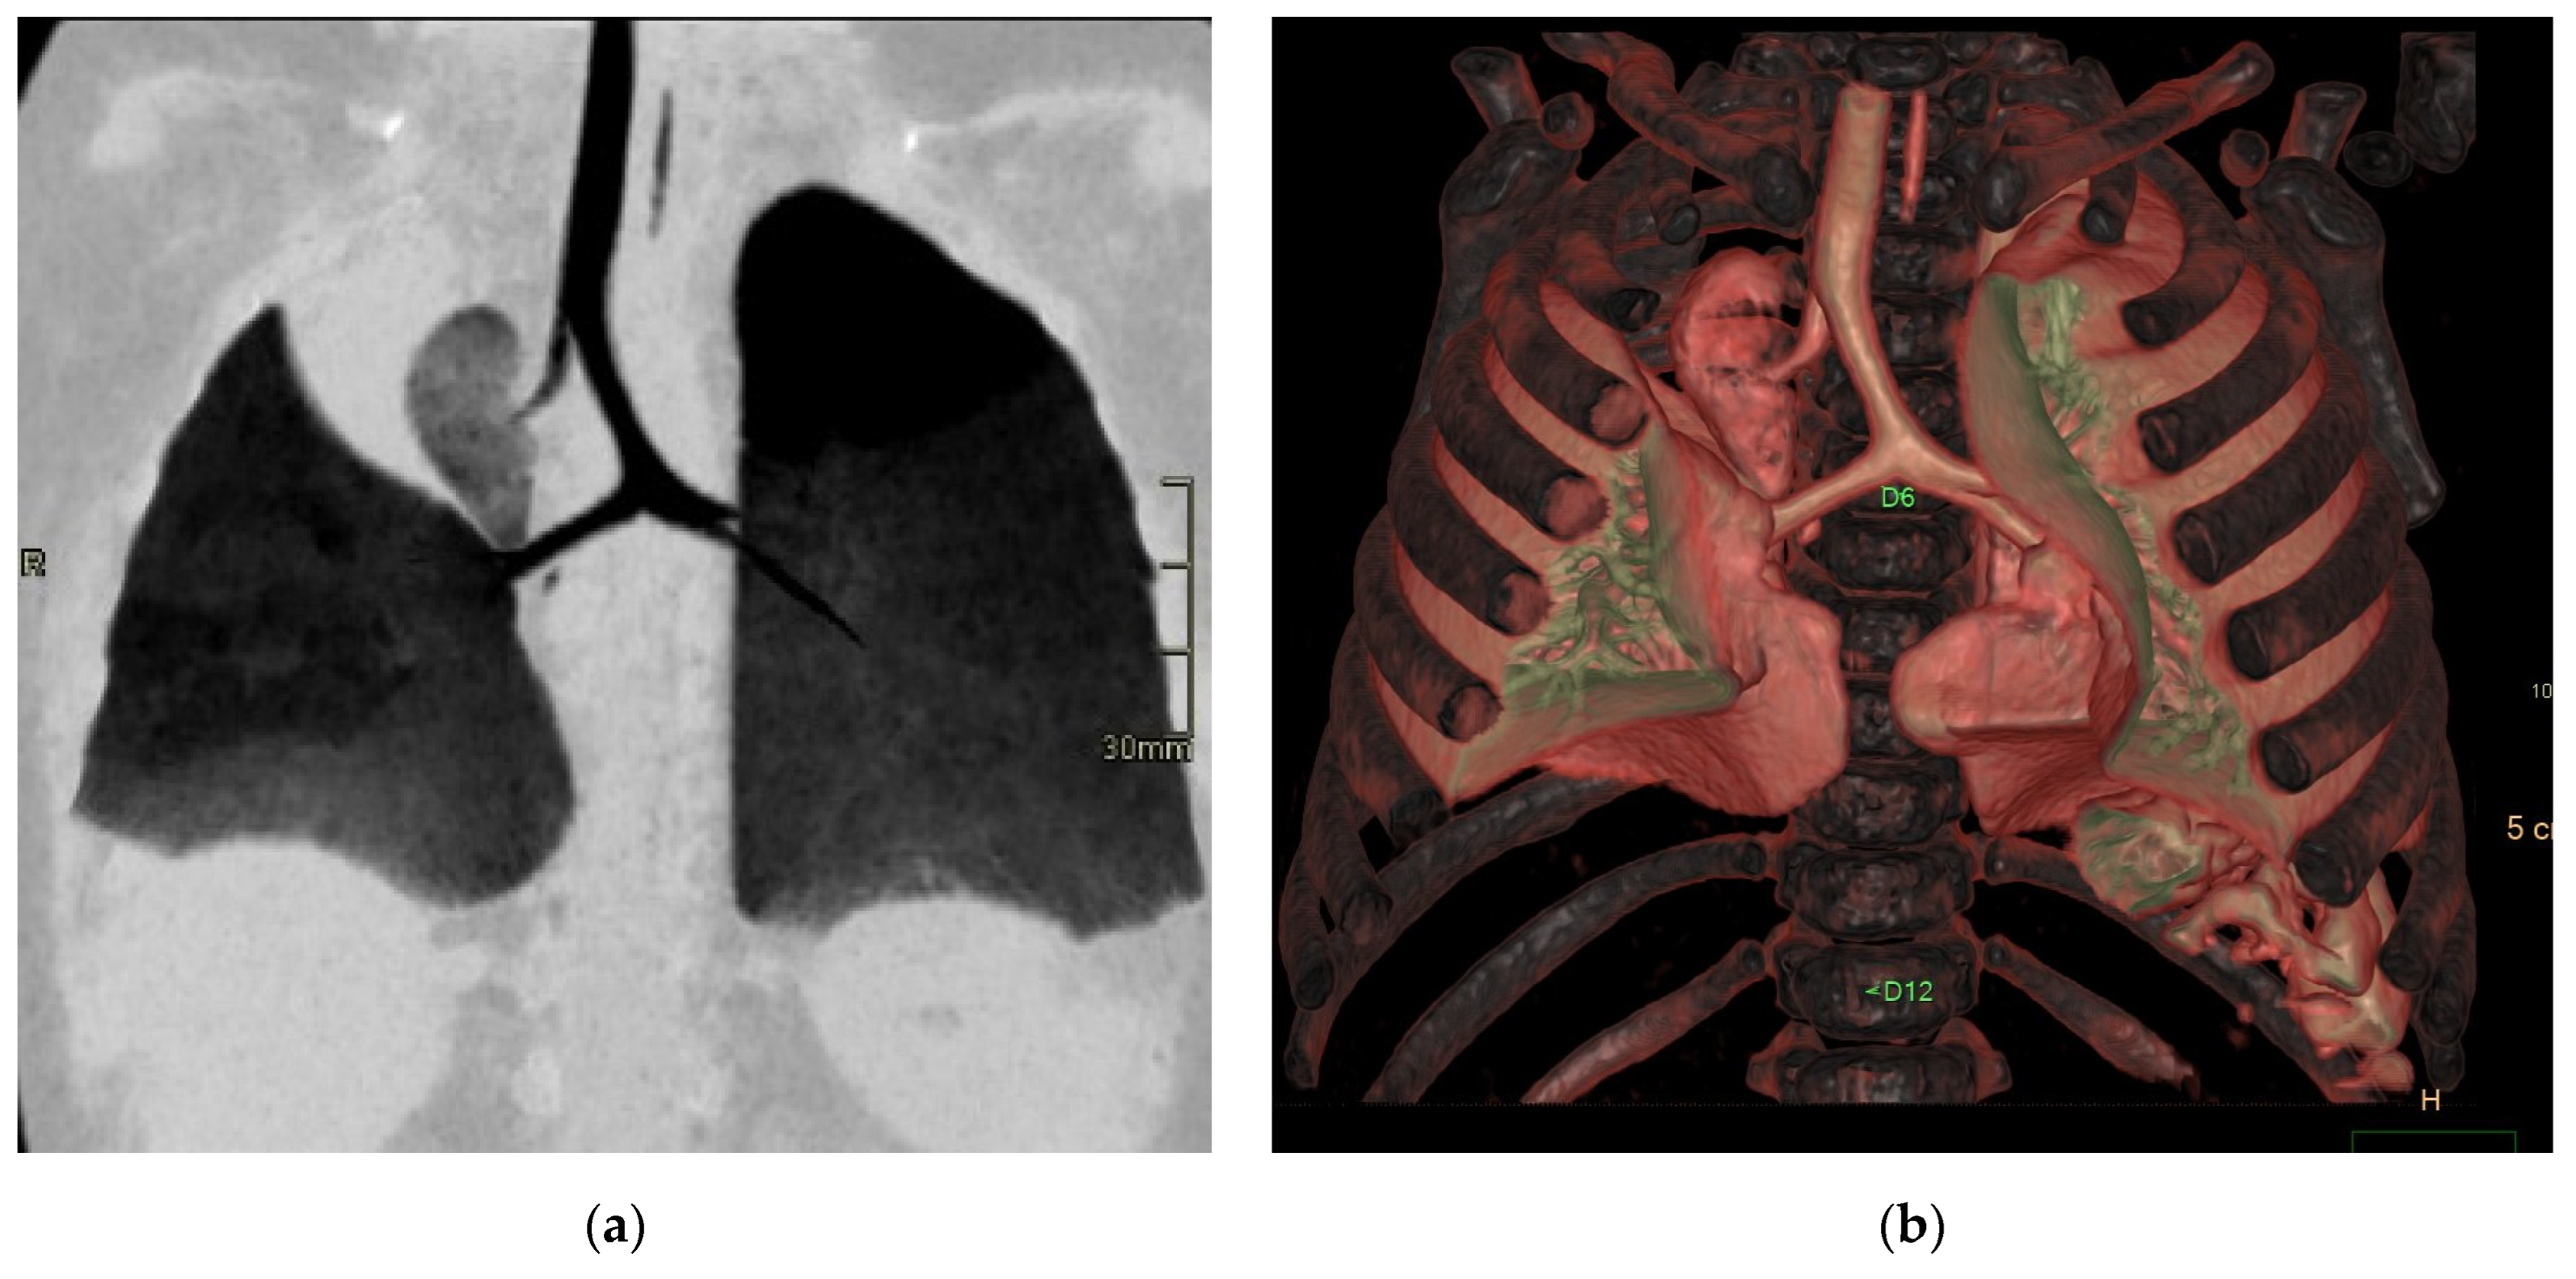

Figure 9. Bridging bronchus type 2. Non-contrast CT coronal (a) and VR (b) images reveal the RMB ending in a diverticulum. The right lung is ventilated by a displaced RMB arising from the LMB, forming a pseudo-carina, that is at the T6–T7 level and has an inverted T appearance.

In type 1, the right main bronchus (RMB) terminates in the right upper lobe (ULB), while the intermediate bronchus abnormally arises from the left main bronchus (LMB), creating a pseudocarina; either the right bronchus or a bridging bronchus generally supplies the middle lobe [14]. Type 2 is often associated with right lung hypoplasia (Figure 9). In this type, the RMB may be absent or end in a diverticulum. The entire right lung is ventilated by a displaced RMB originating from the LMB, forming a pseudocarina [14].

In this condition, the carina faces thoracic vertebrae T4 and T5; the pseudocarina, instead, is at the T6–T7 level and has an inverted T appearance [14].